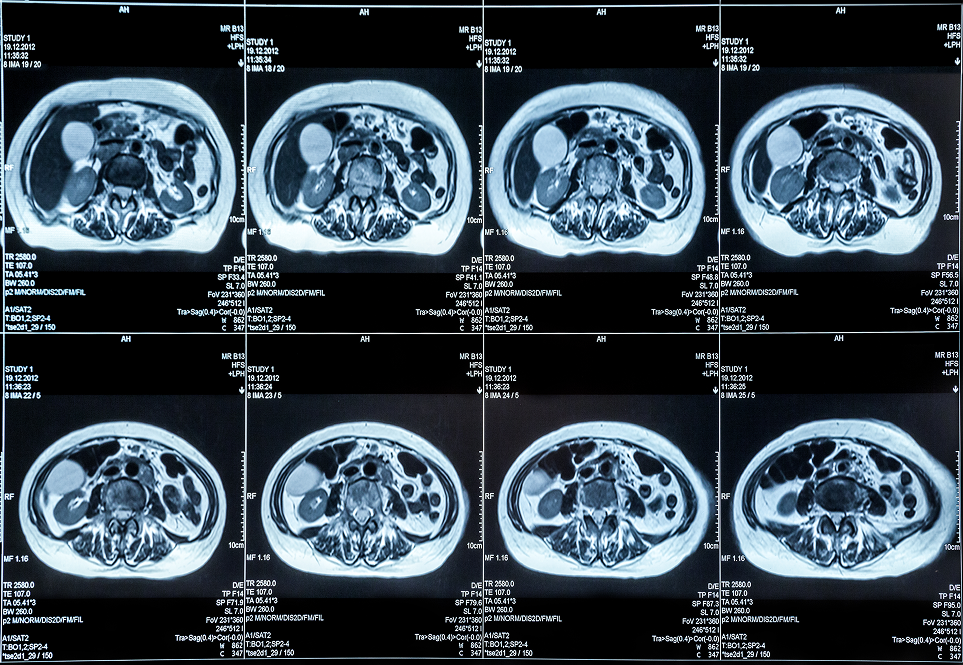

Our cutting-edge segmentation services utilized advanced algorithm platforms to accurately identify and delineate anatomical structures in medical images, which were crucial for effective diagnosis and treatment planning. These technologies enabled us to achieve high levels of accuracy in segmenting anatomical structures and pathological regions within medical images. The applications of medical image segmentation were vast, ranging from Aneurysm detection and organ delineation to the assessment of disease progression. By providing precise segmentation, we empowered healthcare Professionals to make informed decisions regarding diagnosis and treatment planning. We completed many segmentations with accuracy and quality across various parts of the body and different imaging modalities (Such as CT, MRI, DSA, etc.) covering a range of pathologies (Such as Occlusion, Infarct, Dissection, etc.) in multiple types of imaging (CTA, NCCT, MRA, etc.).

- CT Scan Segmentation for detecting lung diseases, tumors, and fractures.

- Combining CT Scan Segmentation, MRI Image Segmentation, and PET scans to enhance diagnostic capabilities.